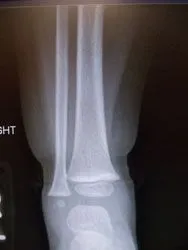

The two pics below are of a nondisplaced subtle toddler tibia fracture. There is a spiral oblique fracture of the distal tibia

Xrays of nondisplaced toddler fracture